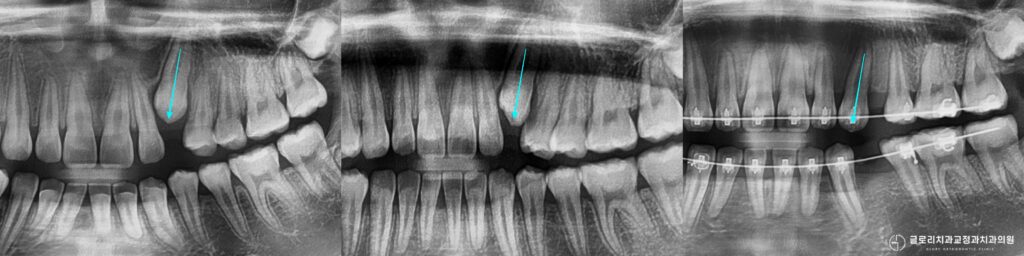

상봉역 교정치과 구치부 염증으로 인한 발치 후 교정 : 골격성 2급부정교합 개선 총과정

안녕하세요.상봉역 교정 치과 김정은 원장입니다.🙂 교정 상담을 진행하다보면 치아가 삐뚤하다 앞니가 많이 덮인다 같은 고민으로 시작되는 경우가 많습니다. 하지만 막상…